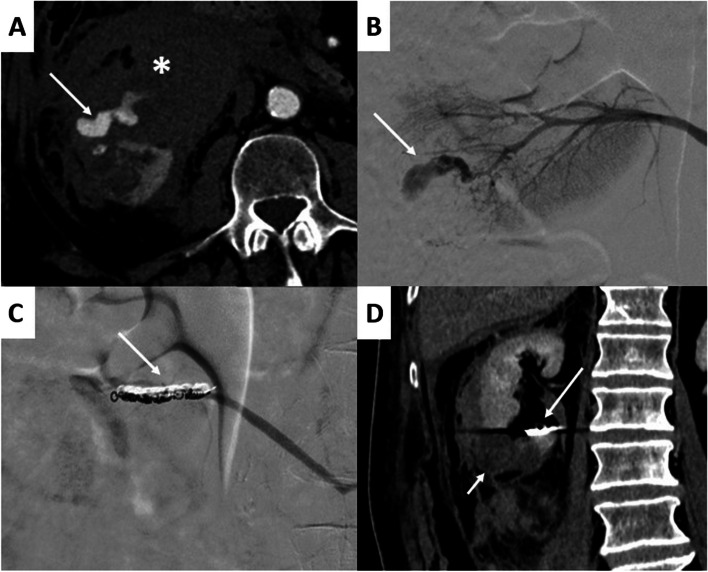

Results: During the inclusion period, 79 procedures were performed. The median age was 60[39-73] years old. On preoperative CT, ≥ 1 pseudoaneurysm was detected in 36(45.6%) patients, and active bleeding in 47(65.8%) patients. The preoperative median haemoglobin rate was 8.9[7.6-11] g/dl, and 37(46.8%) patients required red blood cell transfusions. The main aetiologies of arterial injury were blunt trauma (n = 19) and renal biopsy (n = 17). No severe adverse events were reported. Clinical success was reported in 74(93.7%) of the procedures. Three (3.8%) repeat embolizations were required, and were clinically successful. During the median follow-up of 7[1.5-35.5] months, 9(11.4%) patients died, of which 5(6.3%) occurred within 30 days.

Abstract Image